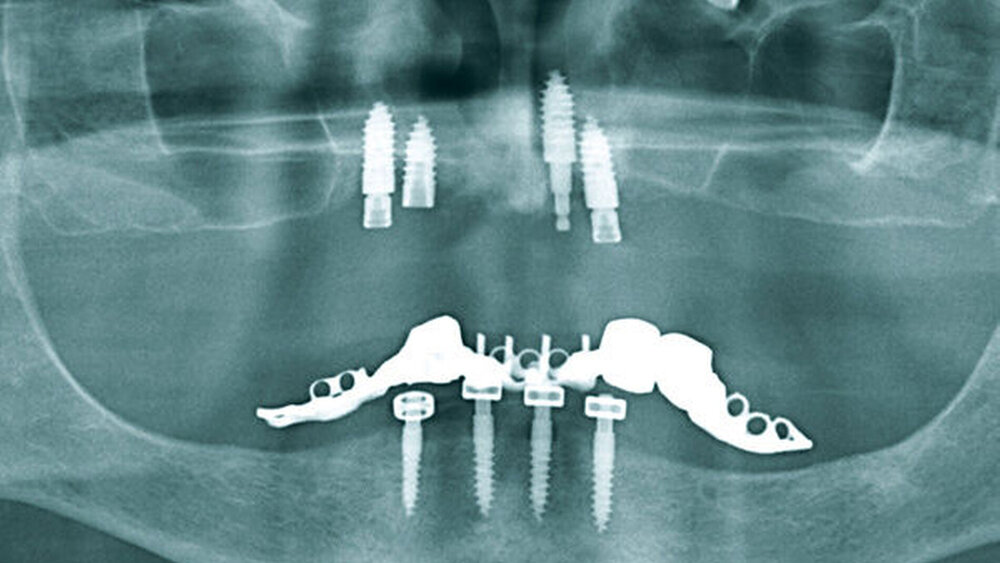

Bei der klinischen Untersuchung zeigten sich beide Kiefer totalprothetisch versorgt. Im Ober- und im Unterkiefer waren zur prothetischen Verankerung jeweils vier Implantate inseriert worden. In der durchgeführten Panoramaschichtaufnahme (PAN) zeigten sich alle Implantate osseointegriert. Zusammen mit den klinischen Befunden ergab sich kein Hinweis auf eine Periimplantitis oder einen weiteren Infektfokus. Die im Bereich des linken Sinus maxillaris nebenbefundlich festgestellte Opazität erweckte den Verdacht auf das Vorliegen eines metallenen Fremdkörpers in Form eines dentalen Implantats (Abbildung 1).

Bei der klinischen Untersuchung zeigte sich ein Druckschmerz über der linken Kieferhöhle und dem linken Sinus frontalis. In der PAN bestätigten sich eine beidseitige Augmentation der Oberkieferalveolarfortsätze von 17 bis 15 und von 25 bis 27, eine totale Verschattung der linken Kieferhöhle sowie beidseitig im Boden der Kieferhöhlen befindliche metallische Fremdkörper (Abbildung 5).